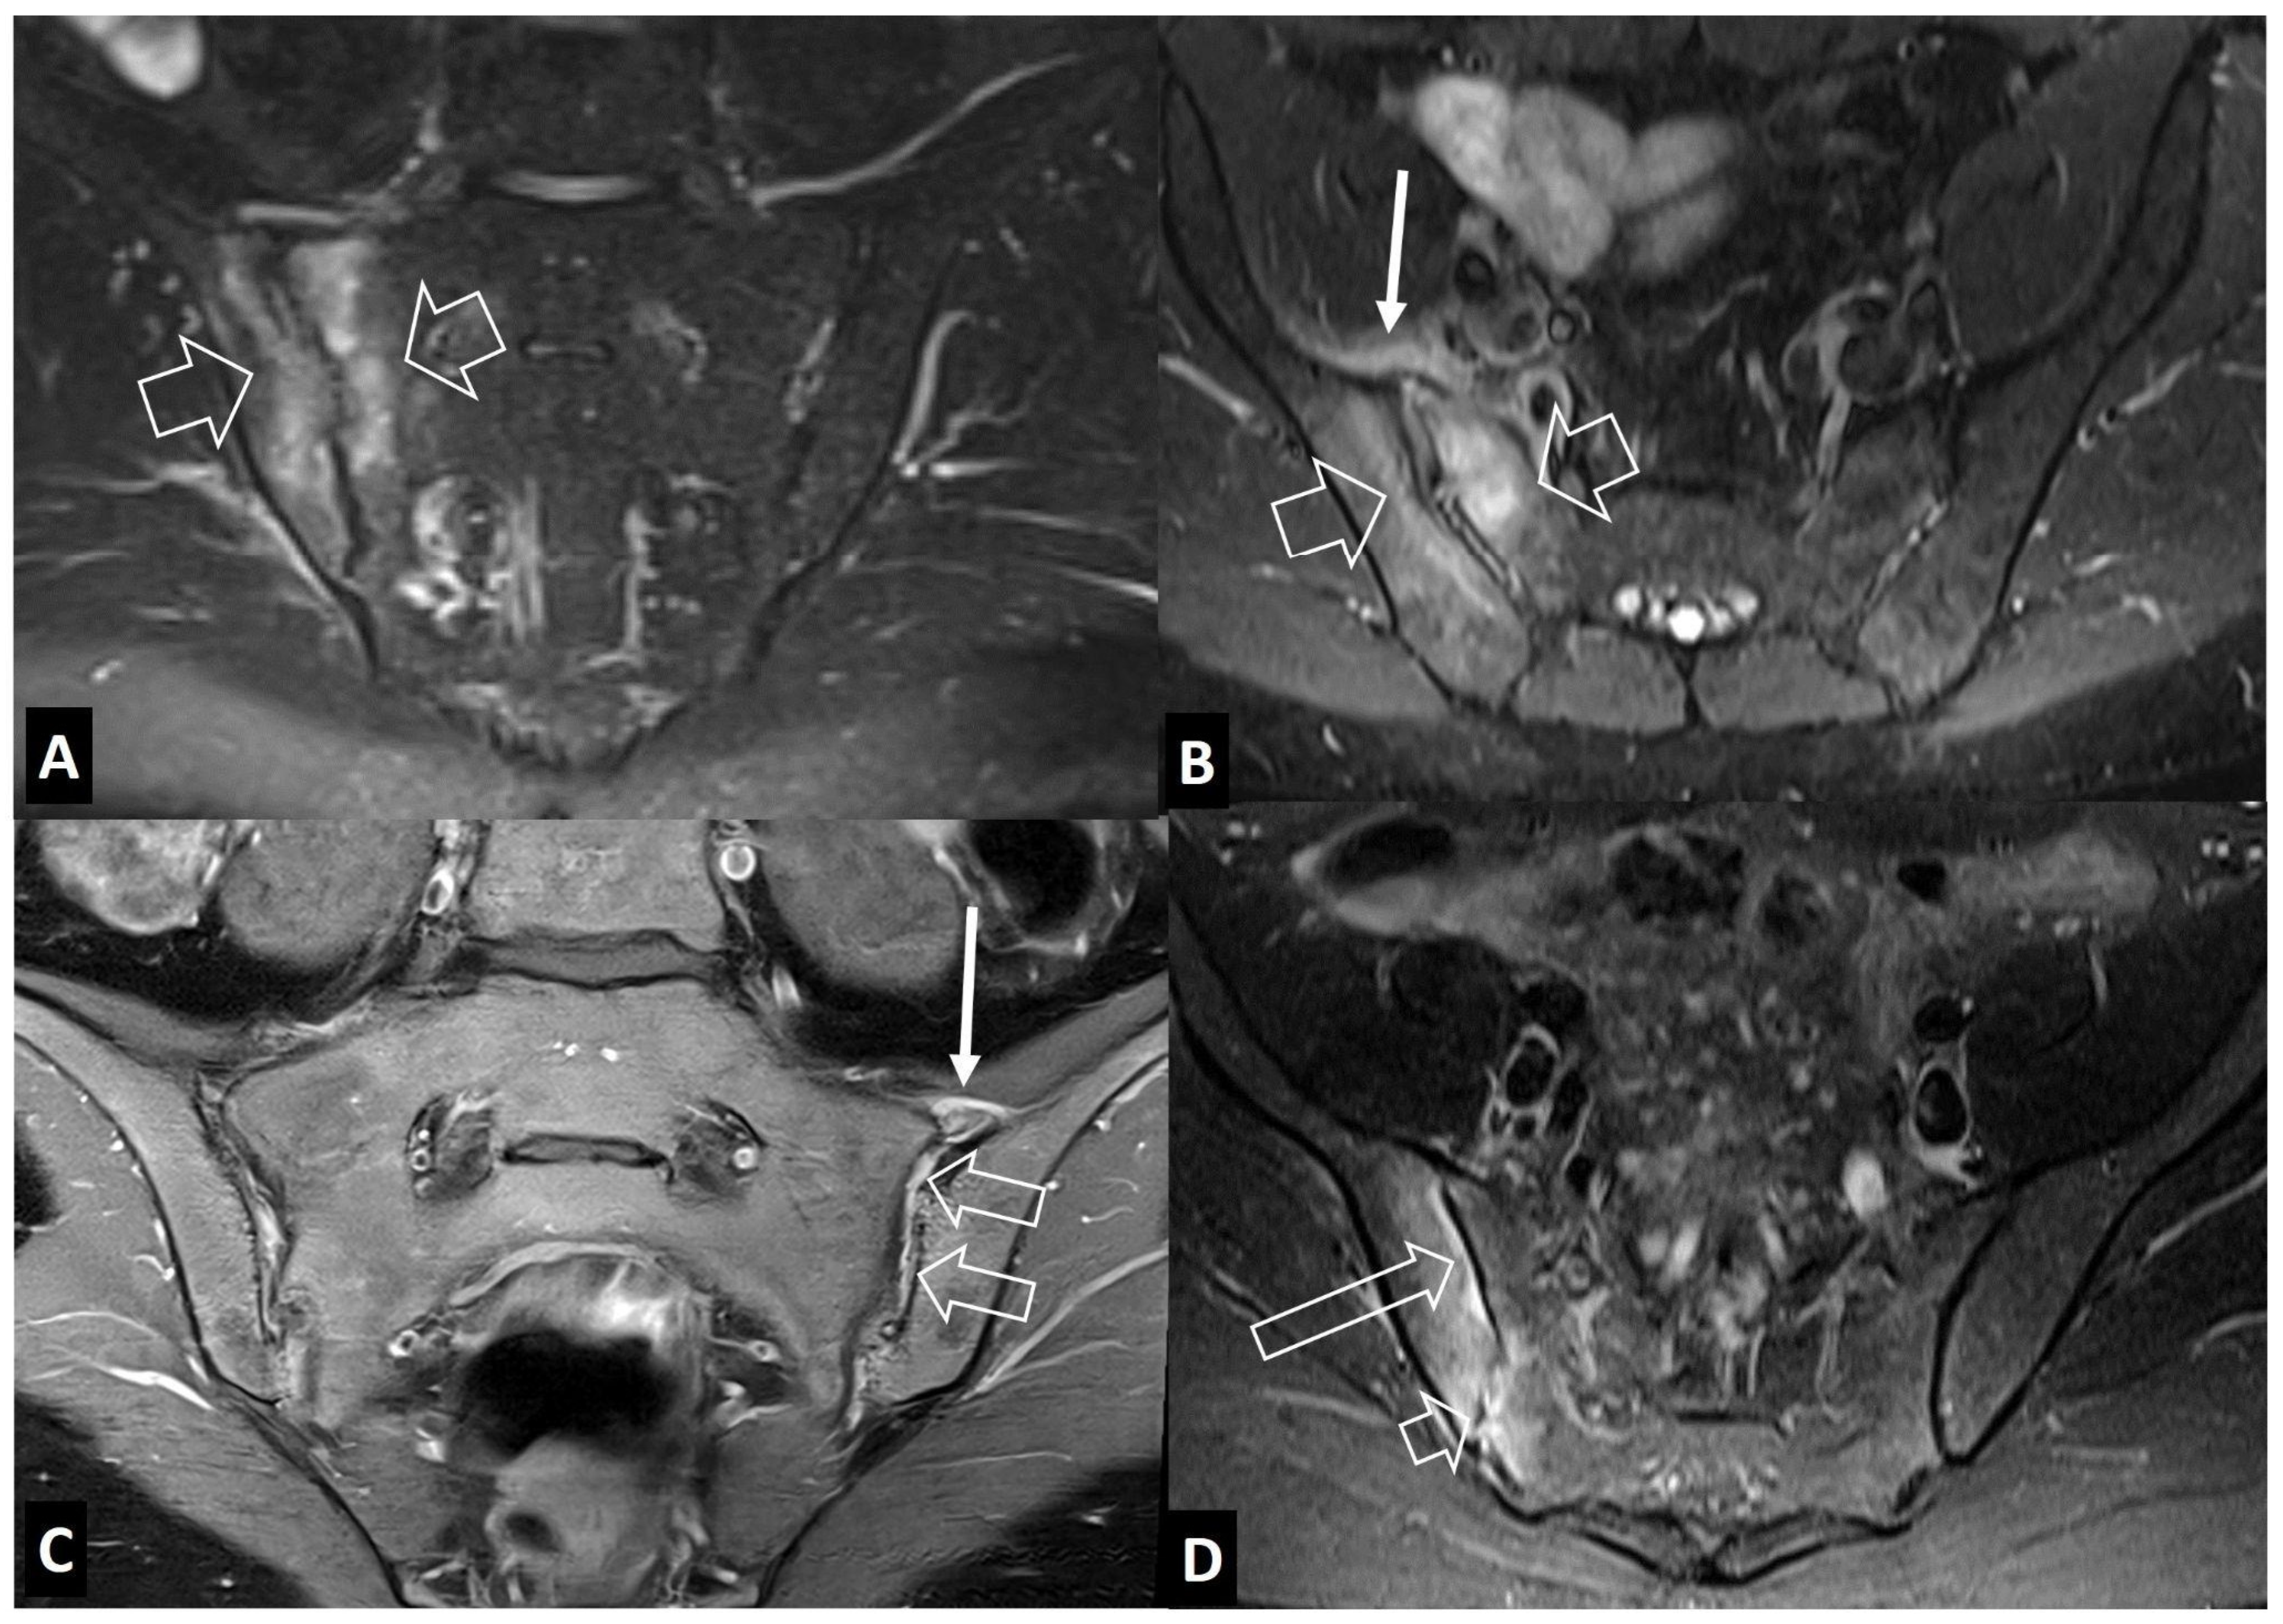

2.2. Non-Infectious Sacroiliitis

- Interligator, S.; Le Bozec, A.; Cluzel, G.; Devilder, M.; Ghaouche, J.; Guenoun, D.; Fleury, A.; Petit Lemaire, F.; Carlier, R.Y.; Valente, C.; et al. Infectious sacroiliitis: MRI- and CT-based assessment of disease extent, complications, and anatomic correlation. Skeletal Radiol. 2023, 53, 2247–2262. [Google Scholar] [CrossRef] [PubMed]

- Kang, Y.; Hong, S.H.; Kim, J.Y.; Yoo, H.J.; Choi, J.-Y.; Yi, M.; Kang, H.S. Unilateral sacroiliitis: Differential diagnosis between infectious sacroiliitis and spondyloarthritis based on MRI findings. AJR Am. J. Roentgenol. 2015, 205, 1048–1055. [Google Scholar] [CrossRef] [PubMed]